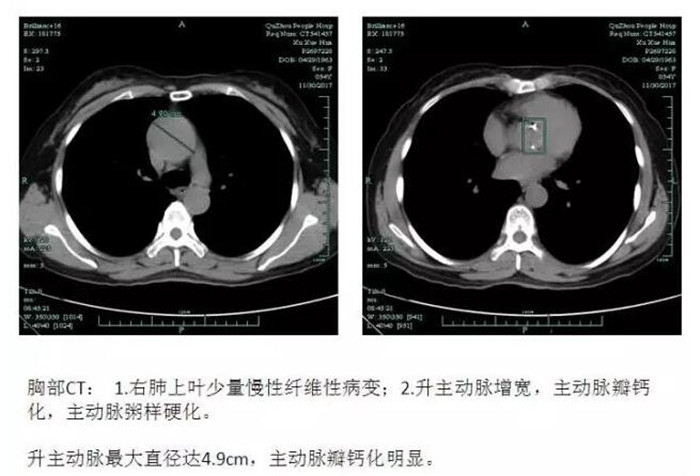

??? 54歲的徐阿姨,3年前開始出現(xiàn)胸悶、氣喘癥狀,一直沒有引起重視。近半年來,徐阿姨勞動時心慌、氣喘等癥狀較之前明顯加重,休息后不能緩解,入住我院心胸外科。檢查后發(fā)現(xiàn)主動脈根部僅2.2cm,主動脈瓣鈣化明顯,呈重度狹窄,主動脈瓣二葉瓣畸形,升主動脈瘤樣擴張,最粗的地方直徑超過4.9cm。若不及時手術治療,隨著病情發(fā)展,會出現(xiàn)心律失常、血栓栓塞,將影響患者的正常生活,嚴重時還會造成心力衰竭,危及生命。

??? 心胸外科副主任周珉為徐阿姨制定了詳細的治療方案。由于主動脈瓣鈣化的存在,同時主動脈根部細小,升主動脈瘤樣擴張,手術過程中極易造成瓣膜切除困難、切除不徹底、鈣化斑塊脫落、主動脈切口出血、瓣膜置入困難等風險,手術難度極大,風險極高。12月5日,周珉帶領其團隊,在麻醉科、手術室、超聲科、輸血科等醫(yī)護人員通力配合下,為徐阿姨行體外循環(huán)下主動脈瓣置換術,手術非常成功!